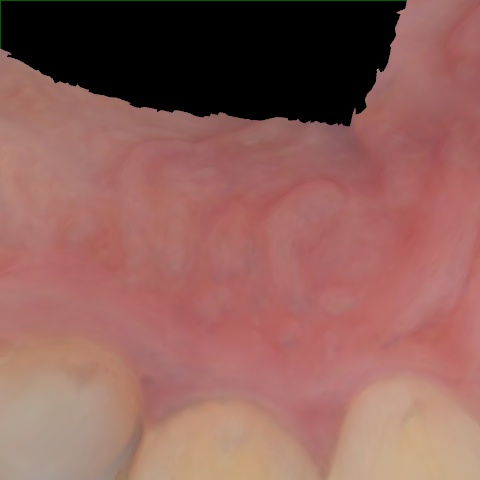

Annotated as "Good"